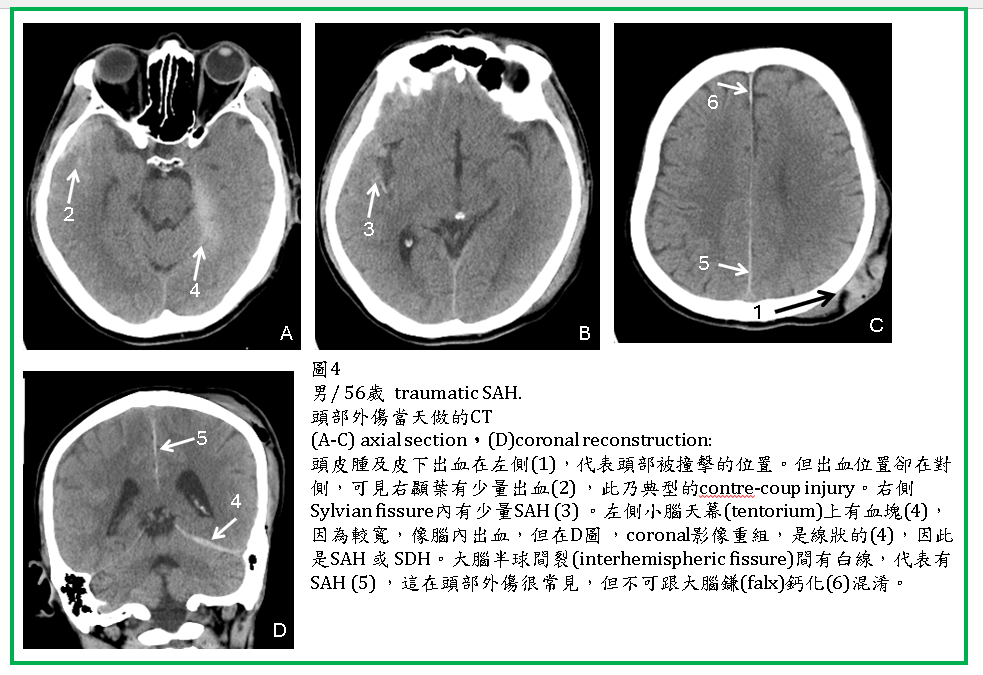

外傷性SAH (Traumatic SAH)

外傷性蜘蛛網膜下腔出血(traumatic subarachnoid hemorrhage, SAH) 很常見,可以單獨發生,但更常合併brain contusion, SDH, EDH。

Traumatic SAH 於CT上常見於大腦腦溝(sulcus),腦裂(Sylvian fissure, interhemispheric fissure),腦池(如suprasellar cistern),以及小腦天幕旁 (tentorial edge)。CT對於SAH及IVH的診斷很敏銳,但在成年人interhemispheric fissures內的falx鈣化與SAH容易混淆。位於tentorium edge 以及interhemispheric fissures內的SAH,與SDH不易區分,coronal reconstruction 有助於鑑別。